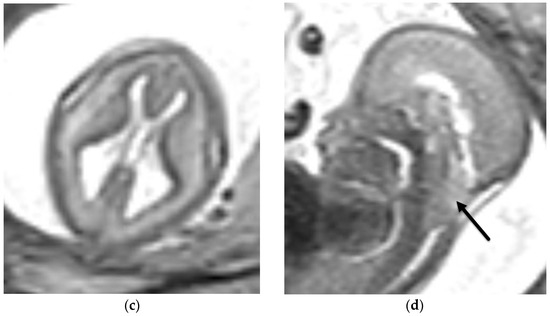

4.1. Holoprosencephaly Spectrum

4.2. Corpus Callosum Anomalies

- Winter, T.C.; Kennedy, A.M.; Woodward, P.J. Holoprosencephaly: A survey of the entity, with embryology and fetal imaging. Radiographics 2015, 35, 275–290. [Google Scholar] [CrossRef]

- Barkovich, A.; Raybaud, C.A. Pediatric Neuroimaging, 6th ed.; Wolters Kluwer Health: Philadelphia, PA, USA, 2019. [Google Scholar]

- Riddle, A.; Nagaraj, U.; Hopkin, R.J.; Kline-Fath, B.; Venkatesan, C. Fetal Magnetic Resonance Imaging (MRI) in Holoprosencephaly and Associations With Clinical Outcome: Implications for Fetal Counseling. J. Child Neurol. 2021, 36, 357–364. [Google Scholar] [CrossRef]